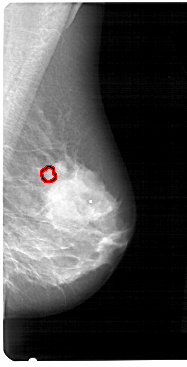

A_1270_1.LEFT_CC

LEFT_CC LINES 5491 PIXELS_PER_LINE 3001 BITS_PER_PIXEL 12 RESOLUTION 43.5 NON_OVERLAY

FILE: A_1270_1.RIGHT_CC.OVERLAY

TOTAL_ABNORMALITIES 1

ABNORMALITY 1

LESION_TYPE CALCIFICATION TYPE PLEOMORPHIC DISTRIBUTION CLUSTERED

ASSESSMENT 4

SUBTLETY 4

PATHOLOGY BENIGN

TOTAL_OUTLINES 1

BOUNDARY